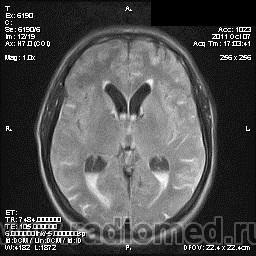

на МРТ - Определяется скопление крови в препонтинной цистерне, в проекции супраселлярной цистерны, в кортикальных бороздах полушарий головного мозга,  в проекции краниоспинального перехода. Выявляется горизонтальный уровень крови в задних рогах боковых желудочков. Боковые, третий желудочки резко расширены. Определяется перивентрикулярное повышение интенсивности сигнала от белого вещества головного мозга. Срединные структуры не смещены. Кортикальные борозды умеренно сглажены. Сильвиев водопровод прослеживается на всем протяжении. Отмечается смещение дна третьего желудочка каудально, с резким уменьшением размеров супраселлярной цистерны; базальные цистерны уменьшены в размере.

В проекции базальной артерии определяется аневризма размером до 4х6 мм.

Я не вижу участки скопления крови, а можно стрелочками указать, для особых не опытных ))) И аневризму стрелочкой пожалуйста. И все таки что за режим последней аксиальной? Tirm ( flair) ? Задние рога боковых желудочков мне не нравятся - но не ужели так кровь у вас видна ?

Мне напоминает FLAIR. В желудочках уровни крови и белое по субарахноидальным щелям тоже кровь. Аневризму тоже не вижу. Может долихоэктазия, если смотреть на сагитталы. Мелковато для меня, наверное.

А почему если это кровь то на т1 она не гиперинтенсивная, и на т2 она нет изменения сигнала? Гиперинтенсивный сигнал на FLAir в субарахноидальных я б подумала что глиозные изменения, но опять же я не вижу изменений на т2 ви. Или правда мелковато и мне не видно? Извините заранее я не спорю с заключением, просто пытаюсь разобраться - заодно и научиться